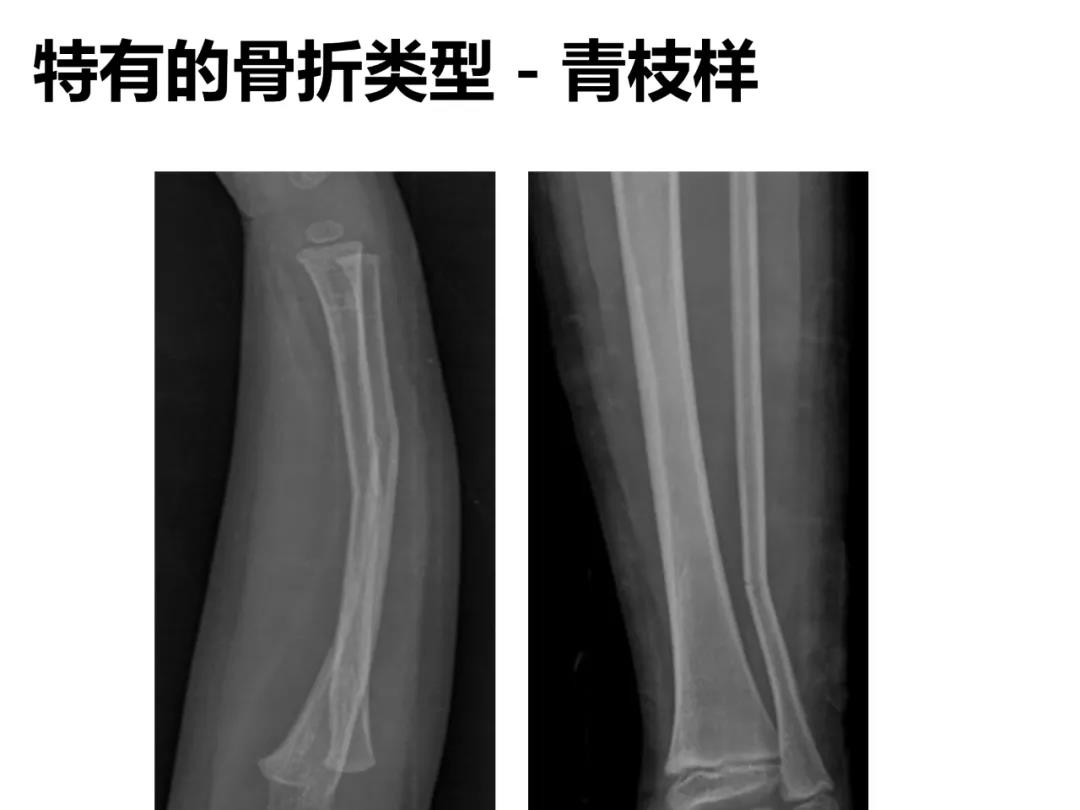

小儿骨科X线片汇总,临床读片宝典!